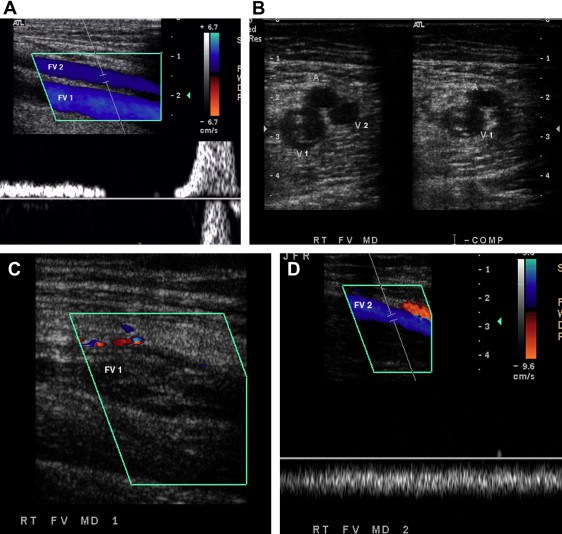

Trong các nghiên cứu tập trung, lớn, độ chính xác của siêu âm ép đối với huyết khối tĩnh mạch sâu có độ đặc hiệu 95% tới 98% và độ nhạy 88-100 % (8).

Các dấu hiệu chẩn đoán siêu âm của huyết khối cấp tính tĩnh mạch sâu bao gồm: không thể ép xẹp các tĩnh mạch và nhìn thấy huyết khối. Huyết khối có thể trống âm, giảm âm hoặc tăng âm.

Hình 3: (A) Siêu âm Doppler màu cắt dọc tĩnh mạch đùi có hai nhánh (FV). (B) Siêu âm cắt ngang hai nhánh tĩnh mạch đùi, một nhánh có huyết khối nên không ép xẹp được (FV1). (C) Siêu âm Doppler màu cắt dọc nhánh FV1. (D) Siêu âm Doppler màu cắt dọc FV2 thấy dòng chảy bình thường.